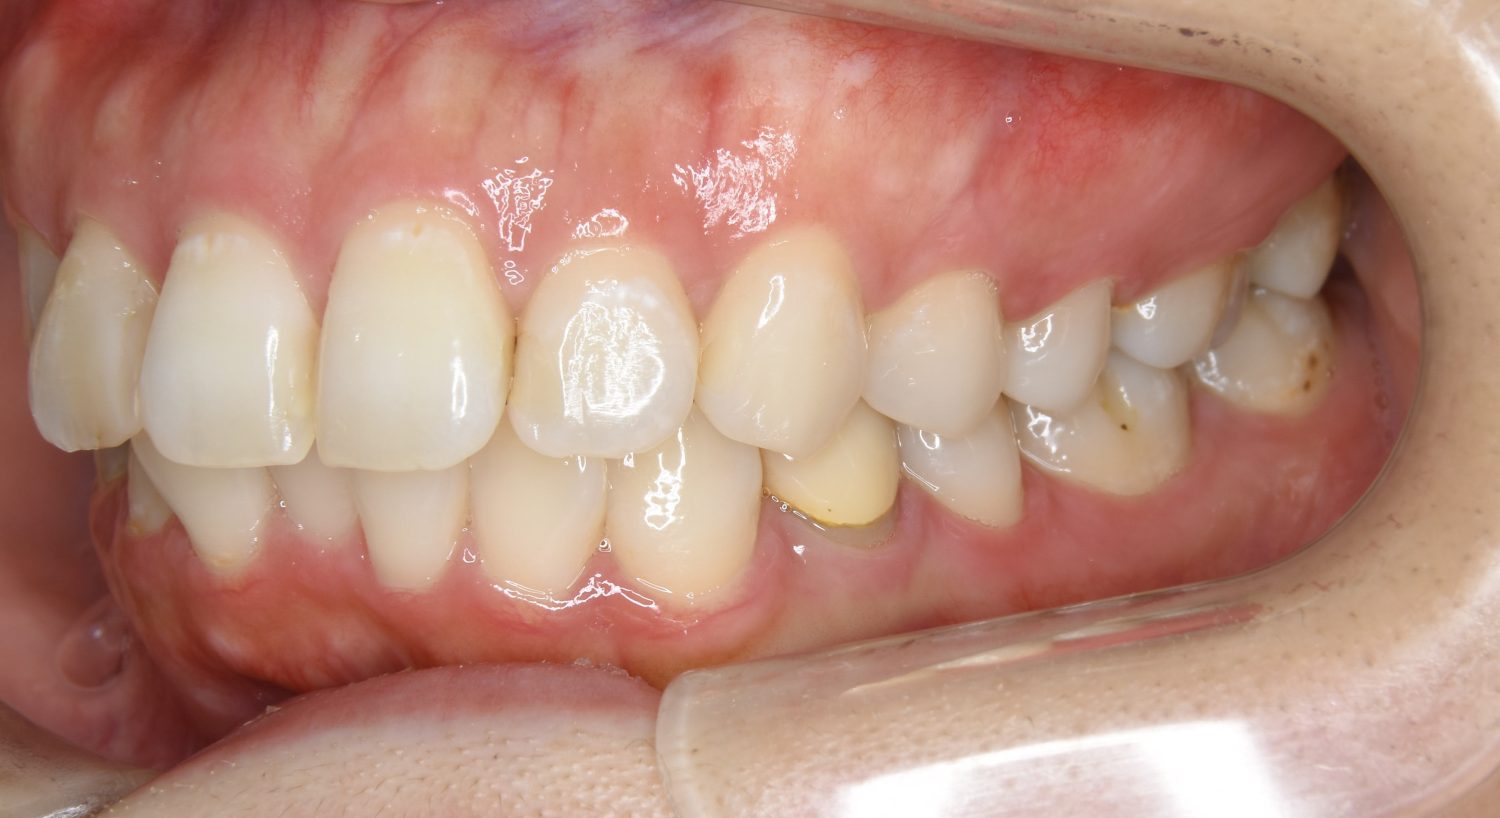

Before

左上の側切歯が完全に内側に入り込んでいる状態でした。左上の第一小臼歯のみ抜歯を行い治療を行うことで機能面および審美面を改善しました。